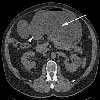

Diagnostic studies. A CT scan ofthe abdomen reveals a markedly dilatedstomach with an obstructive massin the descending portion of the duodenum;these findings are consistentwith gastric outlet obstruction (Figure2). In addition, biliary and pancreaticductal dilatation and multiple livermasses are noted. Esophagoduodenoscopyshows near complete luminalobstruction by the mass (Figure 3).The scope is unable to pass beyond themarkedly narrowed lumen. Results ofbiopsies of the duodenal mass revealmoderately differentiated invasive adenocarcinoma(Figure 4).